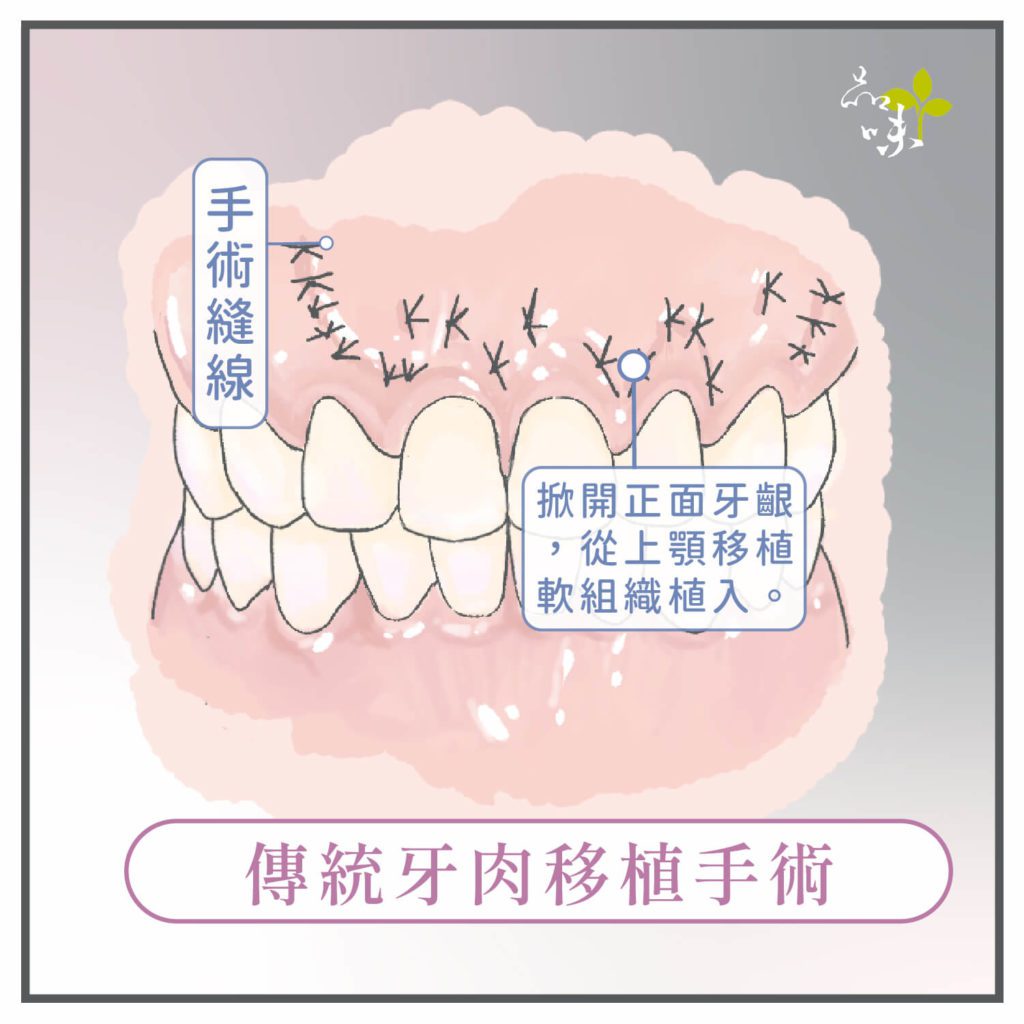

傳統牙肉移植手術

直接移植上顎的軟組織(牙肉)來填補牙根裸露的區域,這種傳統的重建方式已經行之多年,又被稱為「牙根覆蓋手術」。